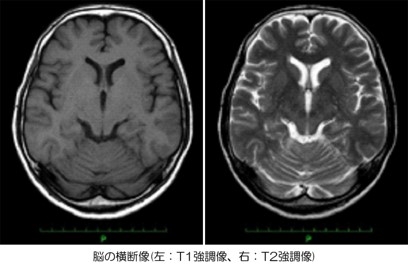

脳.jpg信号の処理方法を変えることで、病変や臓器の

変化を明瞭に捉えることができます。

脳では血流の悪い部分や腫瘍、脊髄の病変などを

確実に診断することができます。